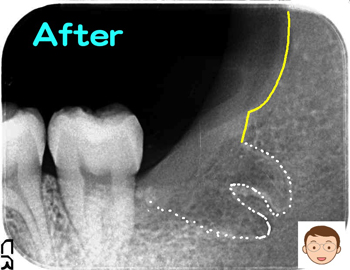

横向きの親知らずの抜歯後にテルプラグ